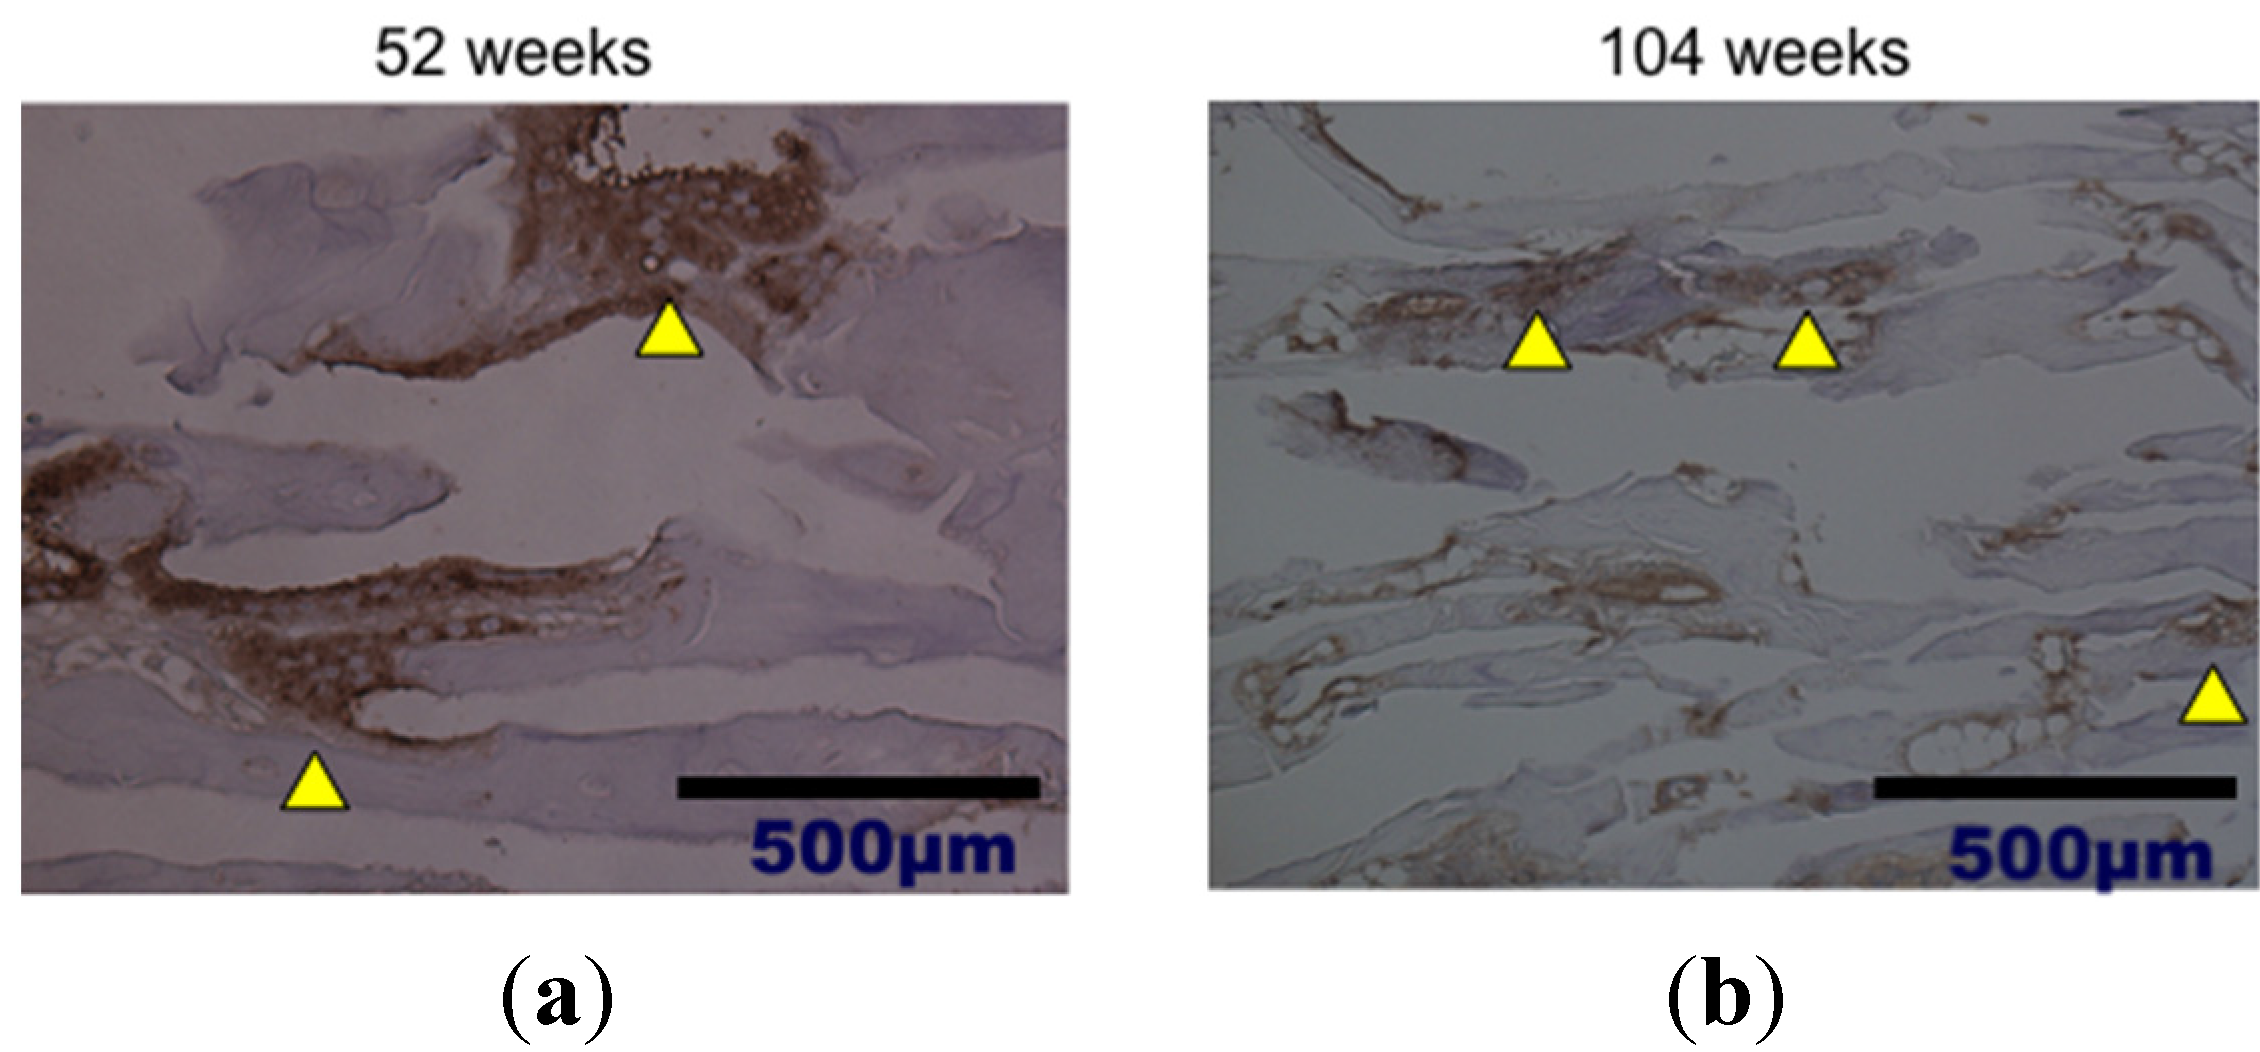

2. Results and Discussion

3.3. Bone Formation in Cortical and Medullary Bone Regions